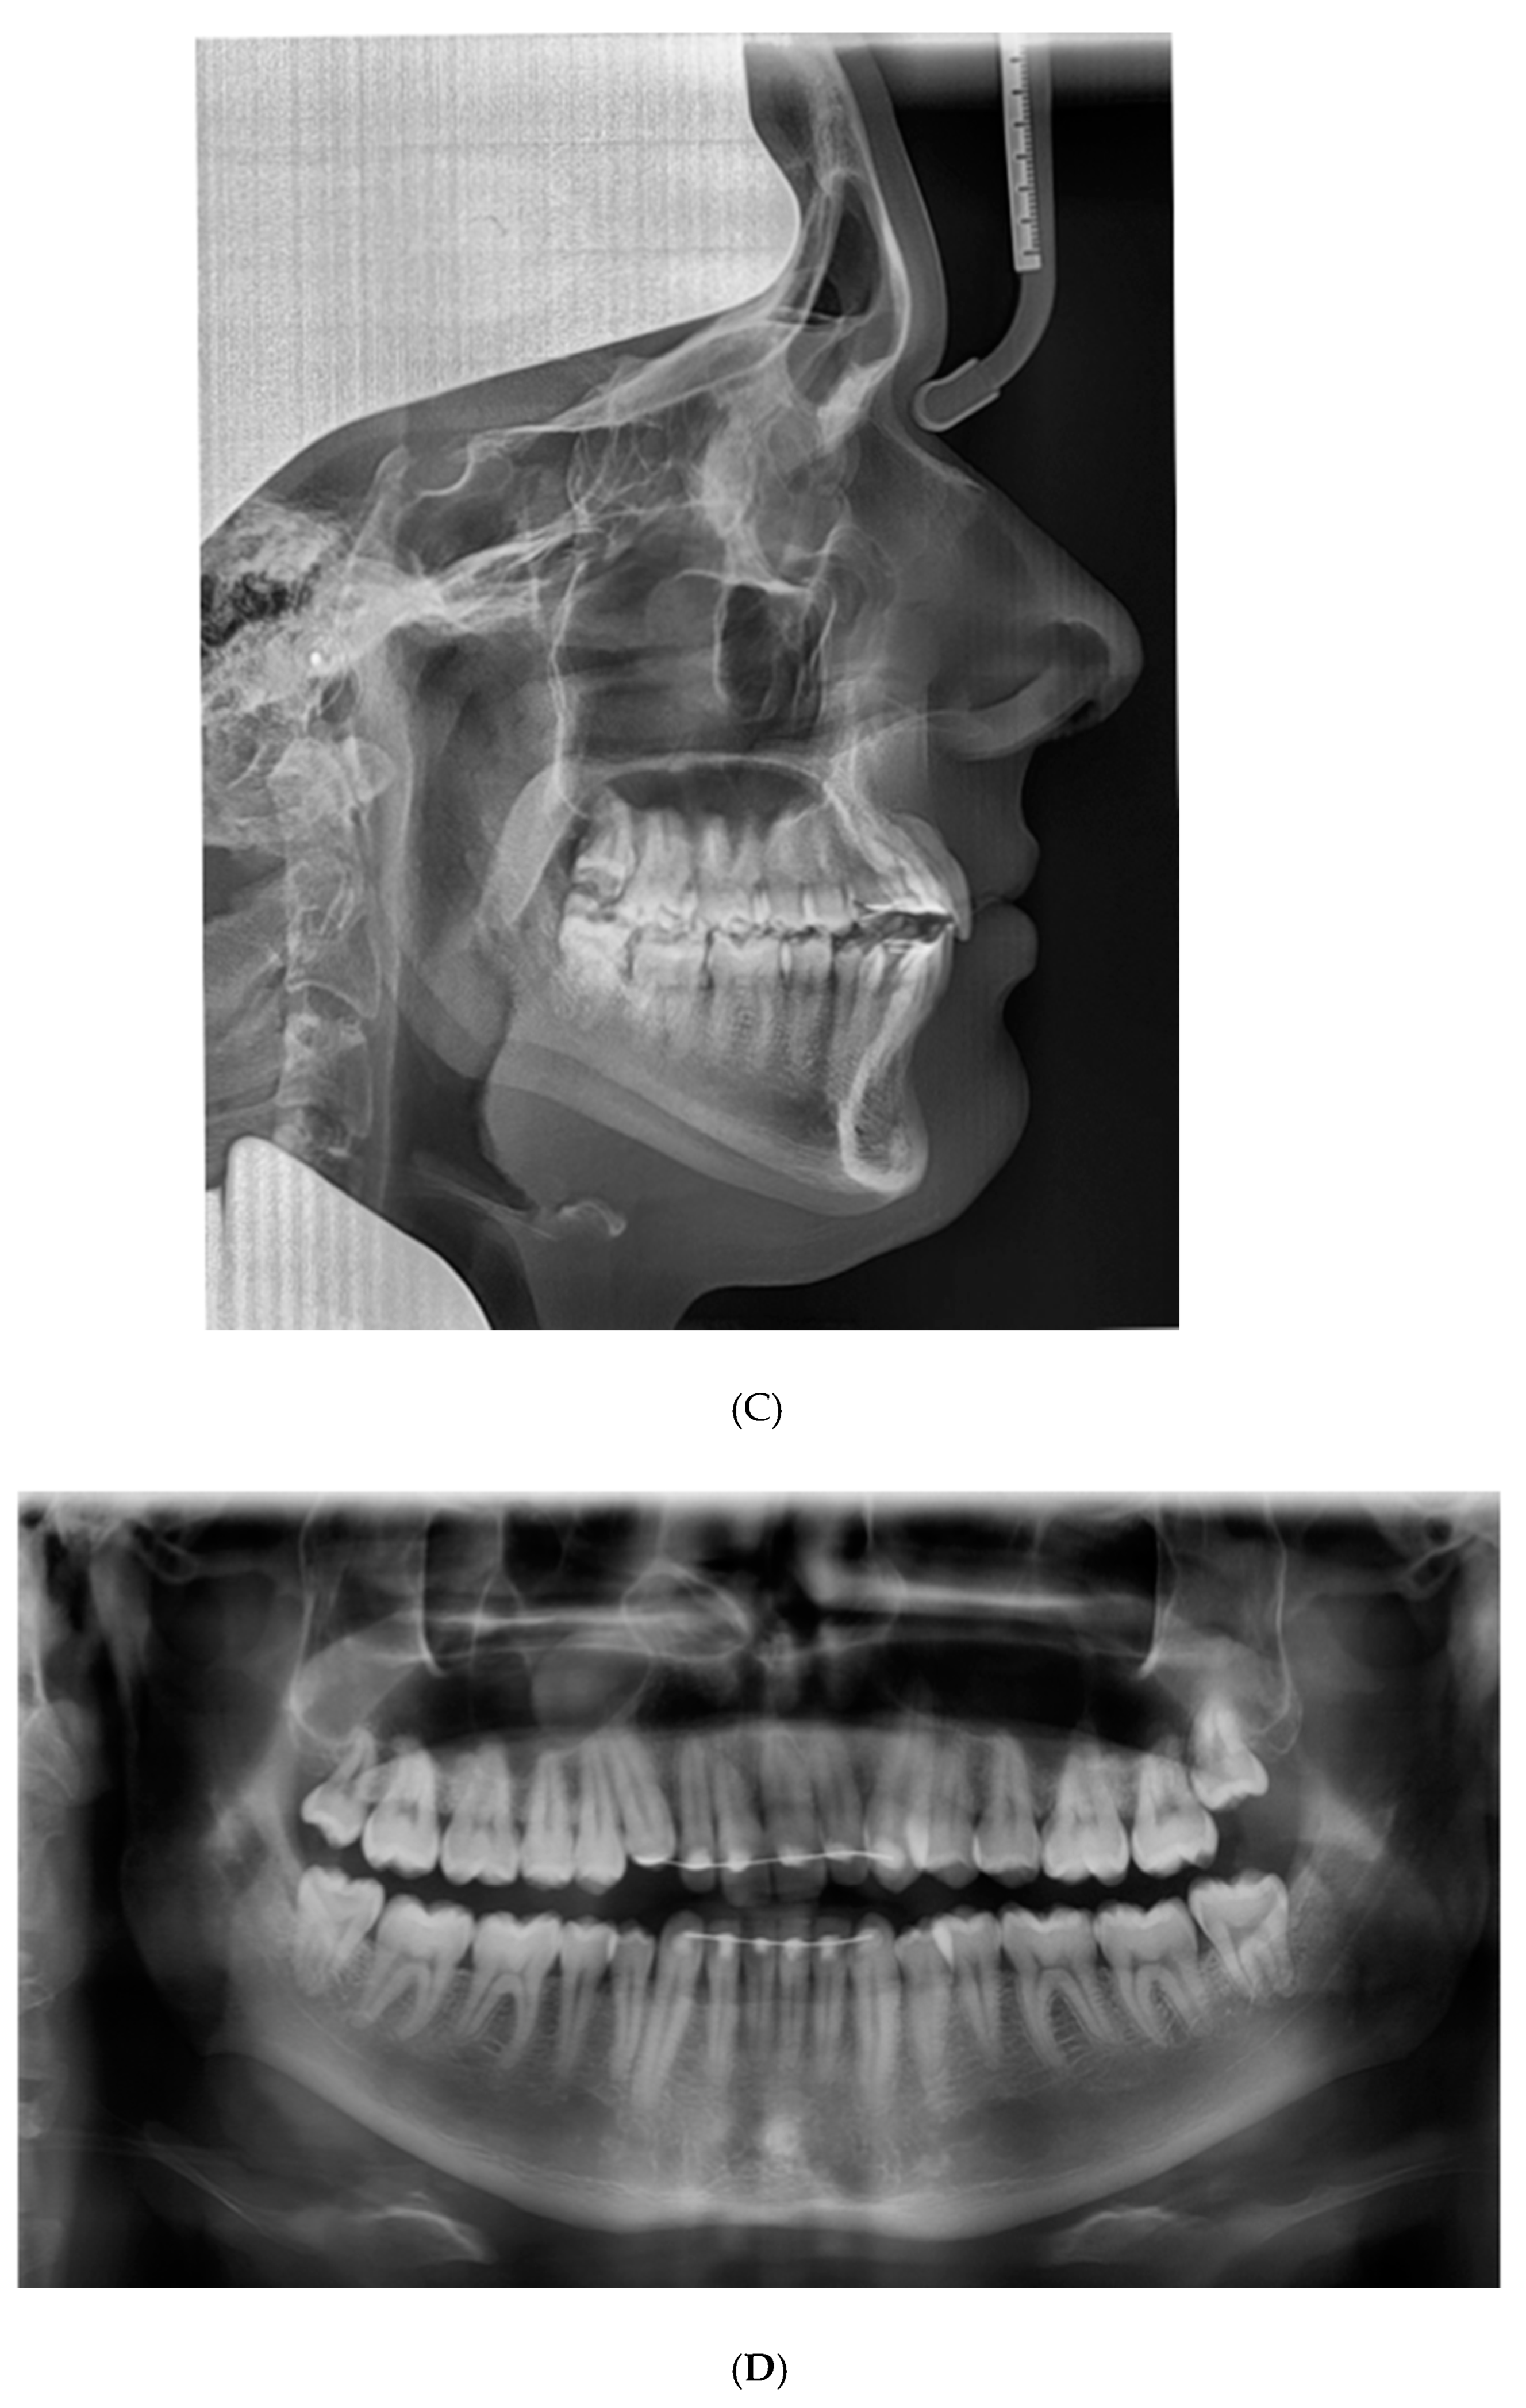

The patient presented with a Class I profile and a chin point deviation to the right side (Figure 3A). The intra-oral assessment showed good oral hygiene, a thin gingival biotype, group function on the left and right side, and fixed retainers (0.0195-inch, 3-strand, heat-treated twist wire, Wildcat, GAC International, Bohemia, NY, USA) in the upper anterior segment and lower anterior segment (Figure 3A). The dental cast assessment showed a Class I molar and canine occlusion, an overjet of 2 mm, and an overbite of 3 mm. A cant of the upper incisors was present with palatal root torque of the 13 and buccal root torque of the 23. Crossbites were present between the 14/44 and the 23/34. The arch length discrepancy measurement resulted in values of 0 mm in the case of the maxillary arch and −4 mm in the case of the mandibular arch. No tooth size discrepancy was present. The PAR index resulted in a score of 12 points [22] (Figure 3B). The lateral cephalometric radiograph showed a Class I intermaxillary relationship with an ANB angle of 3.2° (VistaPano S Ceph, Dürr Dental imaging software, Dürr Dental SE, Bietigheim-Bissingen, Germany) (Figure 3C). The panoramic radiograph (VistaPano S Ceph, Dürr Dental imaging software, Dürr Dental SE, Bietigheim-Bissingen, Germany) showed a maxillary sinus mucosal cyst (MSMC) on the right side and external apical root resorption located at the 12, 11, and 21 (Figure 3D).

Figure 3. Documentation before orthodontic re-treatment. (A) Extra-oral and intra-oral photographs. (B) Dental casts. (C) Lateral cephalometric radiograph. (D) Panoramic radiograph.